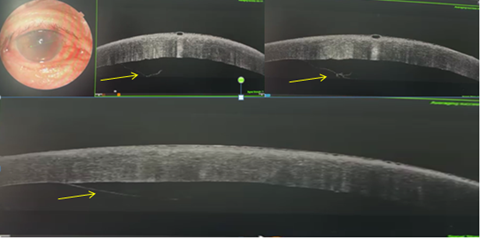

Anterior segment optical coherence tomography (AS-OCT) confirmed a large Descemet’s tear and detachment associated with stromal edema (Figure 2).

Figure 2: AS-OCT image showing extensive Descemet’s membrane detachment (yellow arrows) with stromal edema and early subepithelial bullous changes.

Slit-lamp examination demonstrated regression of corneal edema, with a well-centered intraocular lens and a persistent margin of edema delineating the area of DMD (Figure 3). OCT evaluation revealed partial reapplication of Descemet’s membrane with persistent stromal edema (Figure 4).

Figure 4: AS-OCT after 2 weeks showing partial reattachment of Descemet’s membrane with residual stromal edema and endothelial scarring.